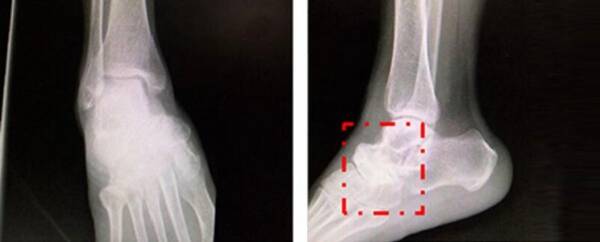

經(jīng)懷集縣人民醫(yī)院進行X線片、CT、MR等傳統(tǒng)影像檢查,初步診斷為:1.右足舟骨壞死。2.右距舟關節(jié)骨關節(jié)炎。3.右跟骰關節(jié)骨關節(jié)炎。擬行右距舟關節(jié)、跟骰關節(jié)融合術。

圖片來源:丁煥文教授團隊

丁煥文教授團隊結合患者癥狀、體征臨床診斷為Muller-Weiss病。通過3D精準定位確認患者病變部位為附橫關節(jié)。通過會診討論,決定為患者實行“足內(nèi)側柱延長、距舟關節(jié)融合、距骨骰骨融合固定”手術。